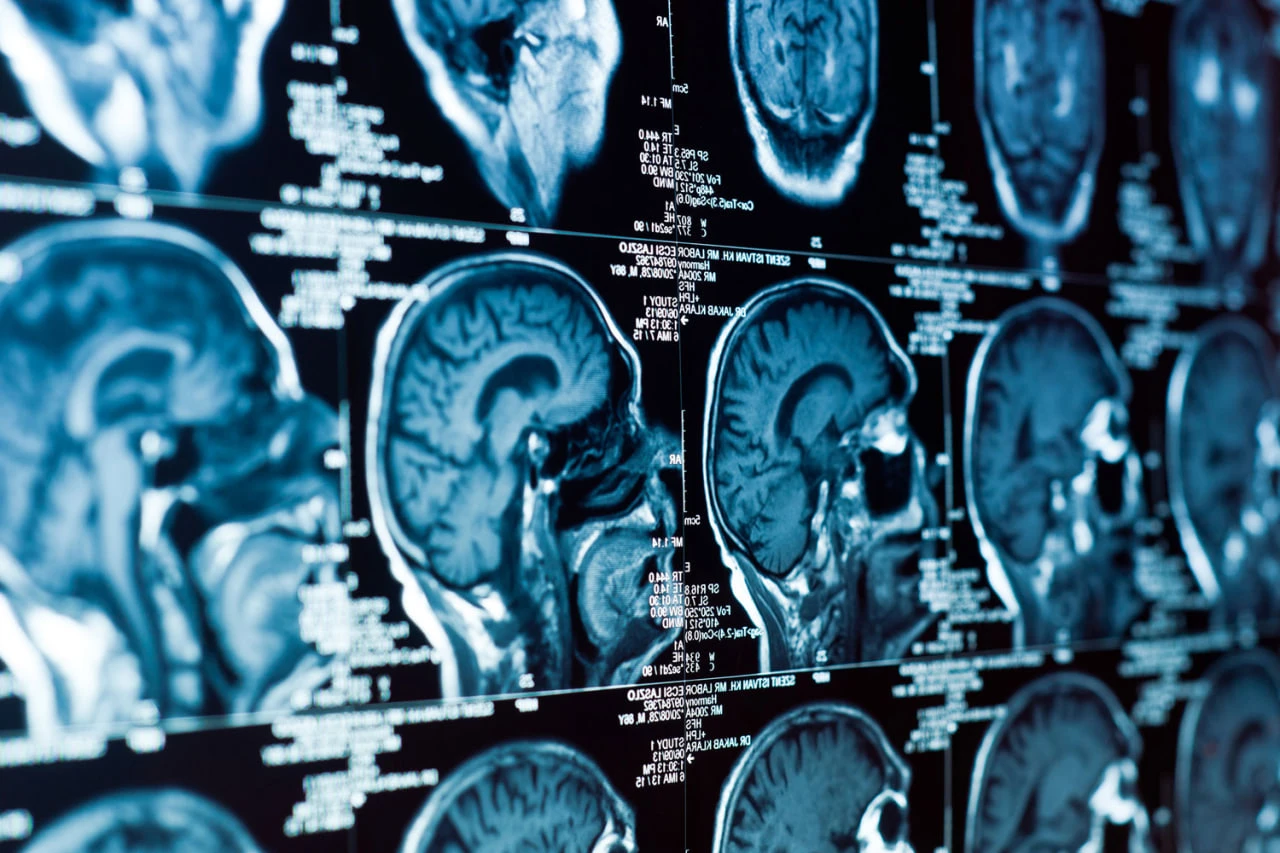

Ученые выяснили, как меняется форма мозга при деменции

Изменения формы мозга с возрастом могут быть связаны с риском развития деменций. К такому выводу пришли Калифорнийский университет (UC IRVINE) и Университет Ла-Лагуна, Университет Лагуны, Испания. Их работа была опубликована в журнале Nature Communications (Natcom).

Более 2600 анализов МР-сканирования мозга позволили ученым проследить, как мозг трансформируется с возрастом и как это связано с результатами когнитивных тестов. Оказалось, что изменения формы мозга происходят неравномерно. Некоторые части сжимаются, другие расширяются, причем эти искажения более выражены у людей с признаками когнитивного падения.

«Мы обнаружили, что трехмерный образ работы мозга меняется с возрастом, и эти изменения глубоко влияют на память и суждение», — объясняет Нильс Янсен, нейролог из Университета Ла-Лагуна Нильс Янсен.

Особое внимание исследователи уделили энлихинеальной кожуре — части мозга, которая играет важную роль в формировании памяти. Энтлешинеальный пилинг – один из первых этапов болезни Альцгеймера. Ученые считают, что возрастные изменения мозга могут оказать давление на эту уязвимую зону, создавая условия для накопления и повреждения токсичных белков.

«Если стареющий мозг деформируется так, что оболочка коры «сжимается», это может объяснить, почему он становится центром патологии болезни Альцгеймера», — сказал невролог из Калифорнийского университета в Ирвайне Майкл Джасан.

Это исследование потенциально может изменить подход к диагностике нейродегенеративных заболеваний. Авторы подчеркивают, что понимание геометрии мозга может сыграть важную роль в раннем выявлении Деменции, а не только в оценке ее последствий.